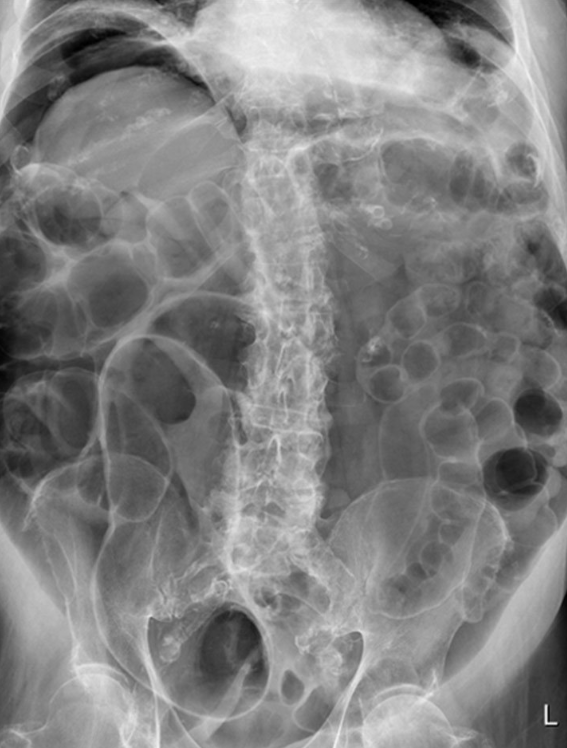

This abdominal X-ray demonstrates multiple dilated loops of bowel with clear valvulae connivente markings. The large bowel is collapsed. **This indicated small bowel obstruction.**